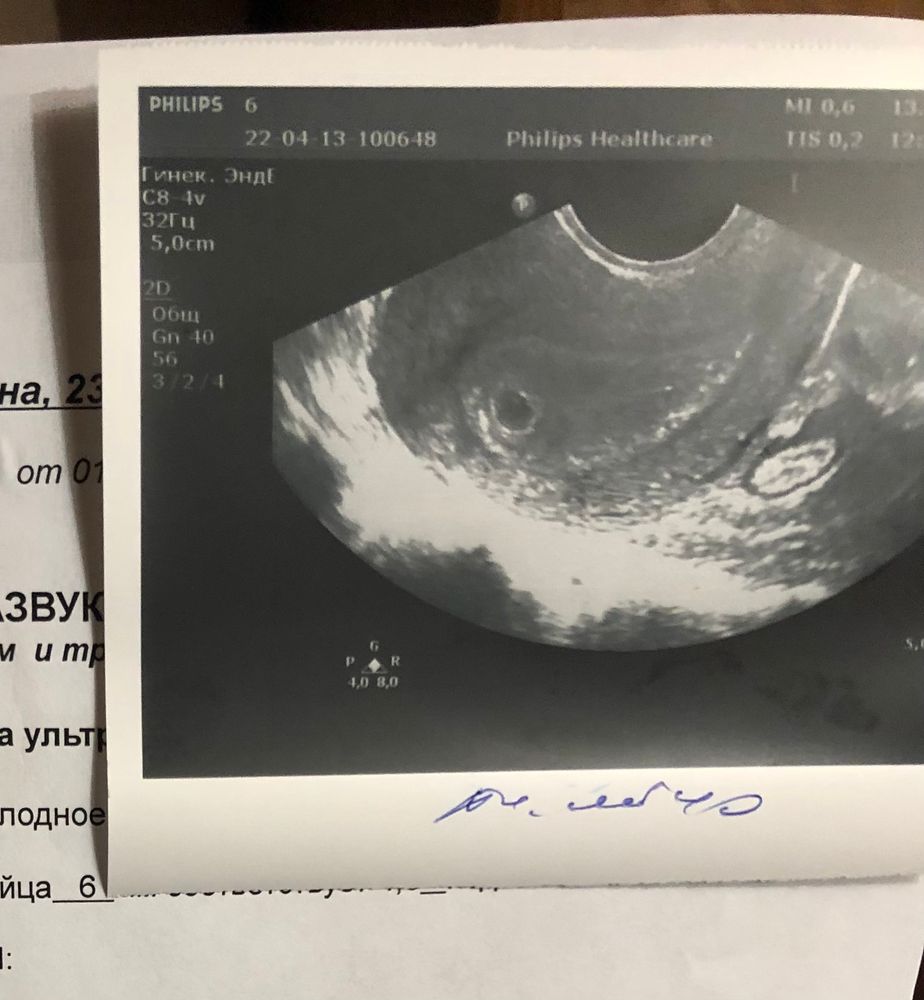

Всем привет. Ранее писала свою историю, в дневнике есть. Сейчас была на узи.

Говорю узисту, что меня уже все настроили(врачи), что ждать особо нечего, но вдруг что-то найдём. Она сказала: «ну почему же нечего ждать, вот, ваше плодное яйцо»

поворачивает экран, а там оно. Масенькое. 6 мм. И она сказала, что все в порядке, отслойки и угрозы нет, сейчас срок отстаёт на 1,5 недели, но может выровняться потом. 🥺